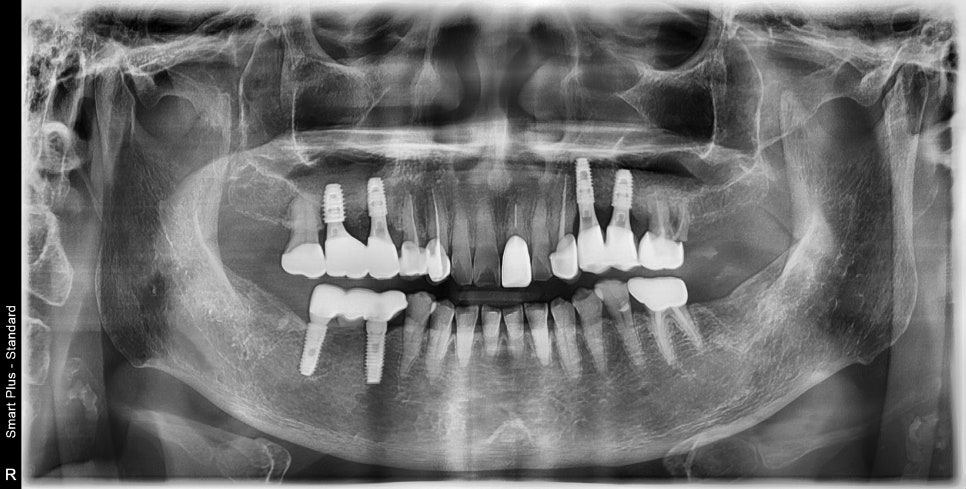

틀니를 쓰실 때보다는 훨씬 식사하시는 것도 편하다 하셨습니다

아직 틀니가 걸렸던 치아들이 흔들리면서 가끔 불편감을 말씀해 주시는데

아직은 이 상태로도 식사는 가능하셔서 최대한 써보시다

불편하면 그때 다른 부위는 치료하기로 하고 관리만 잘해드리기로 했습니다

사진과 같이 틀니로 인해 염증 있는 치아의 제거와 임플란트 치료 전후 사진입니다

염증으로 인한 과증식된 잇몸은 건강한 잇몸으로 바뀌었고

새로운 보철물 또한 교합을 균형 있게 맞추어 앞쪽 치아에 무리가 안 가게 했습니다